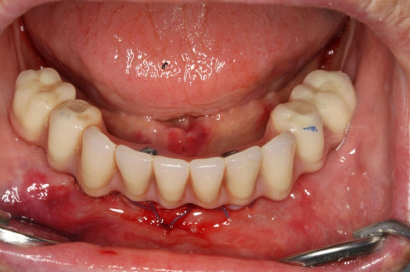

Klasickým příkladem a indikací pro použití implantátu je ztráta jednoho zubu (v tomto případě v předním – frontálním úseku) v jinak zdravém, nepoškozeném chrupu.

Nejčastější příčinou takové ztráty je sportovní nebo dopravní úraz.

Náhrada jednoho zubu pomocí implantátu je možná také v postranním úseku chrupu. Při ztrátě většího počtu zubů ve frontálním nebo postranním úseku může být mezer uzavřena větším počtem jednotlivých implantátů.

Při ošetření pomocí jednotlivých implantátů zůstávají sousední zuby neporušené – intaktní. Při klasickém ošetření pomocí můstků musejí být tyto zuby obroušeny!